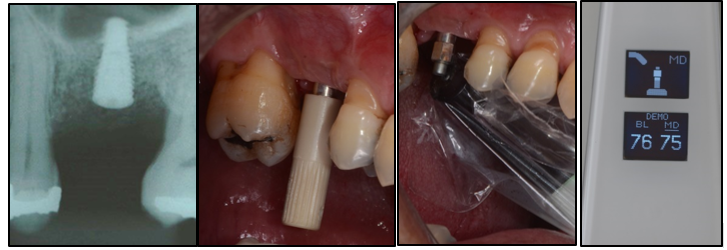

Este aparelho utiliza uma medida para indicar a estabilidade: o ISQ – Quociente de Estabilidade do Implante. Com este equipamento, pode-se ter o acompanhamento da evolução da estabilidade mecânica primária para a estabilidade biológica secundária, inclusive para confirmar o seu carregamento antecipado. O valor ISQ objetivo e numérico é obtido através da irradiação eletromagnética de um SmartPeg, uma peça de alumínio com um imã na ponta, que é aparafusado no hexágono/conexão externa ou hexágono/conexão interna do implante, dependendo do tipo de conexão do implante em questão. Figuras 3, 4 e 5.

Estas mensurações ISQ, são variáveis de 1 a 100 através da tecnologia da varredura por frequência de ressonância (RFA) da superfície do implante em contato com o osso. O RFA mede a estabilidade lateral completa do implante.

– Sempre realizar a medição logo após a instalação do implante.

– Para isso, selecionar o correto SmartPeg para o tipo de implante utilizado.

– Com o montador do SmartPeg (Fig. 5), aparafusar o SmartPeg com força manual (4-6 N.cm) no implante.

– Colocar um protetor de biossegurança no Osstell Beacon.

– Posicionar a ponta do Osstell próxima da ponta do SmartPeg e realizar de forma automática a obtenção do valor ISQ na direção BL, e após, na direção MD.

– Após a mensuração logo após a instalação do implante, avaliar os valores de ISQ encontrados e decidir a carga de acordo com as recomendações da literatura (ver Fig.7).

Na Implacil De Bortoli, para o implante hexágono externo 3.3/3.5 é indicado o SmartPeg modelo 26, para implantes hexágono externo 3.75, 4.0, 4.75 e 5.0 SmartPeg modelo 14, para implantes hexágono interno 3.3 e 3.5 SmartPeg modelo 26, e diâmetros 3.75, 4.0, 4.3 SmartPeg 14. Para implante Cone Morse Maestro e Due Cone, o SmartPeg indicado é o modelo 49. Para os componentes protéticos mini-cônico retos, o SmartPeg indicado é o modelo 25.